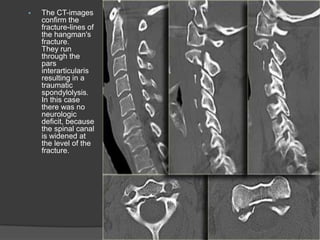

The CT-images

confirm the

fracture-lines of

the hangman's

fracture.

They run

through the

pars

interarticularis

resulting in a

traumatic

spondylolysis.

In this case

there was no

neurologic

deficit, because

the spinal canal

is widened at

the level of the